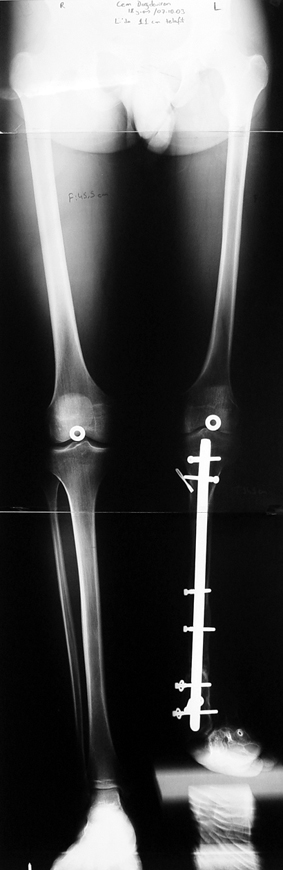

Bu Bacak Kısalık tipi bir kırığın kısalmış pozisyonda kaynaması ile oluşur. Bir çok vaka yetişkinlerde görülür ve sadece bir uzatma ile tedavi edilebilir. Ek deformiteler de aynı anda düzeltilebilir. Bu hastaların çoğu çivi üzerinden uzatma veya tam implante edilen çivi ile tedavi edilebilirler.